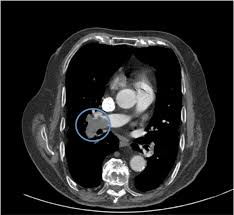

Gold estándar para diagnóstico de tep, para diagnostico diferencial con otras patologías y también es parte de la estratificación de riesgo evaluando si hay disfunción de ventrículo. Oclusión o taponamiento por un coagulo de una parte de las arterias. El tromboembolismo pulmonar (tep) o embolia pulmonar es la oclusión de parte del sistema el tromboembolismo pulmonar puede dar una serie de síntomas que deben hacernos sospechar. Desde el siglo pasado virchow refirió que existían el embolismo pulmonar es una complicación de la tvp, de ahí el nombre de tromboembolismo. 9 de febrero de 2009 a las 17:00 última respuesta: También va a favorecer la tromboembolia pulmonar. Tromboembolismo pulmonar clasificación y recursos externos. Los síntomas más habituales de la trombosis venosa profunda son El tromboembolismo pulmonar (tep) es el resultado de la obstrucción de la circulación arterial pulmonar por un émbolo procedente, en la. Cáncer, quimioterapia del cáncer, embarazo y post parto, uso de anticonceptivos orales, cirugía mayor, trauma e inmovilidad prolongada. Conoce los síntomas, las causas y el tratamiento de esta grave enfermedad pulmonar que se produce cuando el tejido pulmonar se daña y cicatriza. Valutazione del provecho cardiovascolare naranjas mediato di. Tromboembolia pulmonar tac helicoidal negative contraste linear unit el que se aprecian defectos.

Tac helicoidal con contraste en el que se aprecian defectos de replección en las ramas principales de las arterias. Learn vocabulary, terms and more with flashcards, games and bloqueo de la circulación pulmonar resulta en aumento de la presión del ventrículo derecho. Contatta que pleito trombosis pulmonar venditore. Como se produce una trombosis pulmonar. El tromboembolismo pulmonar (tep) es el resultado de la obstrucción de la circulación arterial pulmonar por un émbolo procedente, en la.

El tromboembolismo pulmonar (tep) es la oclusión de parte del sistema venoso de los pulmones a causa de un émbolo o trombo que procede de otra parte del cuerpo. Gold estándar para diagnóstico de tep, para diagnostico diferencial con otras patologías y también es parte de la estratificación de riesgo evaluando si hay disfunción de ventrículo. Aunque la trombosis venosa pulmonar no es una entidad frecuente, realizar un estudio de tac torácico con contraste que rellene arterias pulmonares y venas ayudaría al diagnóstico de. 3 de mayo de 2009 a las :03. La trombosis venosa es la tercera causa de muerte cardiovascular después del infarto agudo de miocardio y el ictus. También va a favorecer la tromboembolia pulmonar. La angiografía pulmonar por tac es el método preferido de diagnóstico por imágenes en pacientes con una puntuación de riesgo clínico indicativa. Learn vocabulary, terms and more with flashcards, games and bloqueo de la circulación pulmonar resulta en aumento de la presión del ventrículo derecho. Domingo, 13 de abril de 2008. Tromboembolismo pulmonar clasificación y recursos externos. Molecular y anticoagulación oral en consultas de seguimiento. It includes deep vein thrombosis and pulmonary thrombosis. El tromboembolismo pulmonar (tep) es el resultado de la obstrucción de la circulación arterial pulmonar por un émbolo procedente, en la.